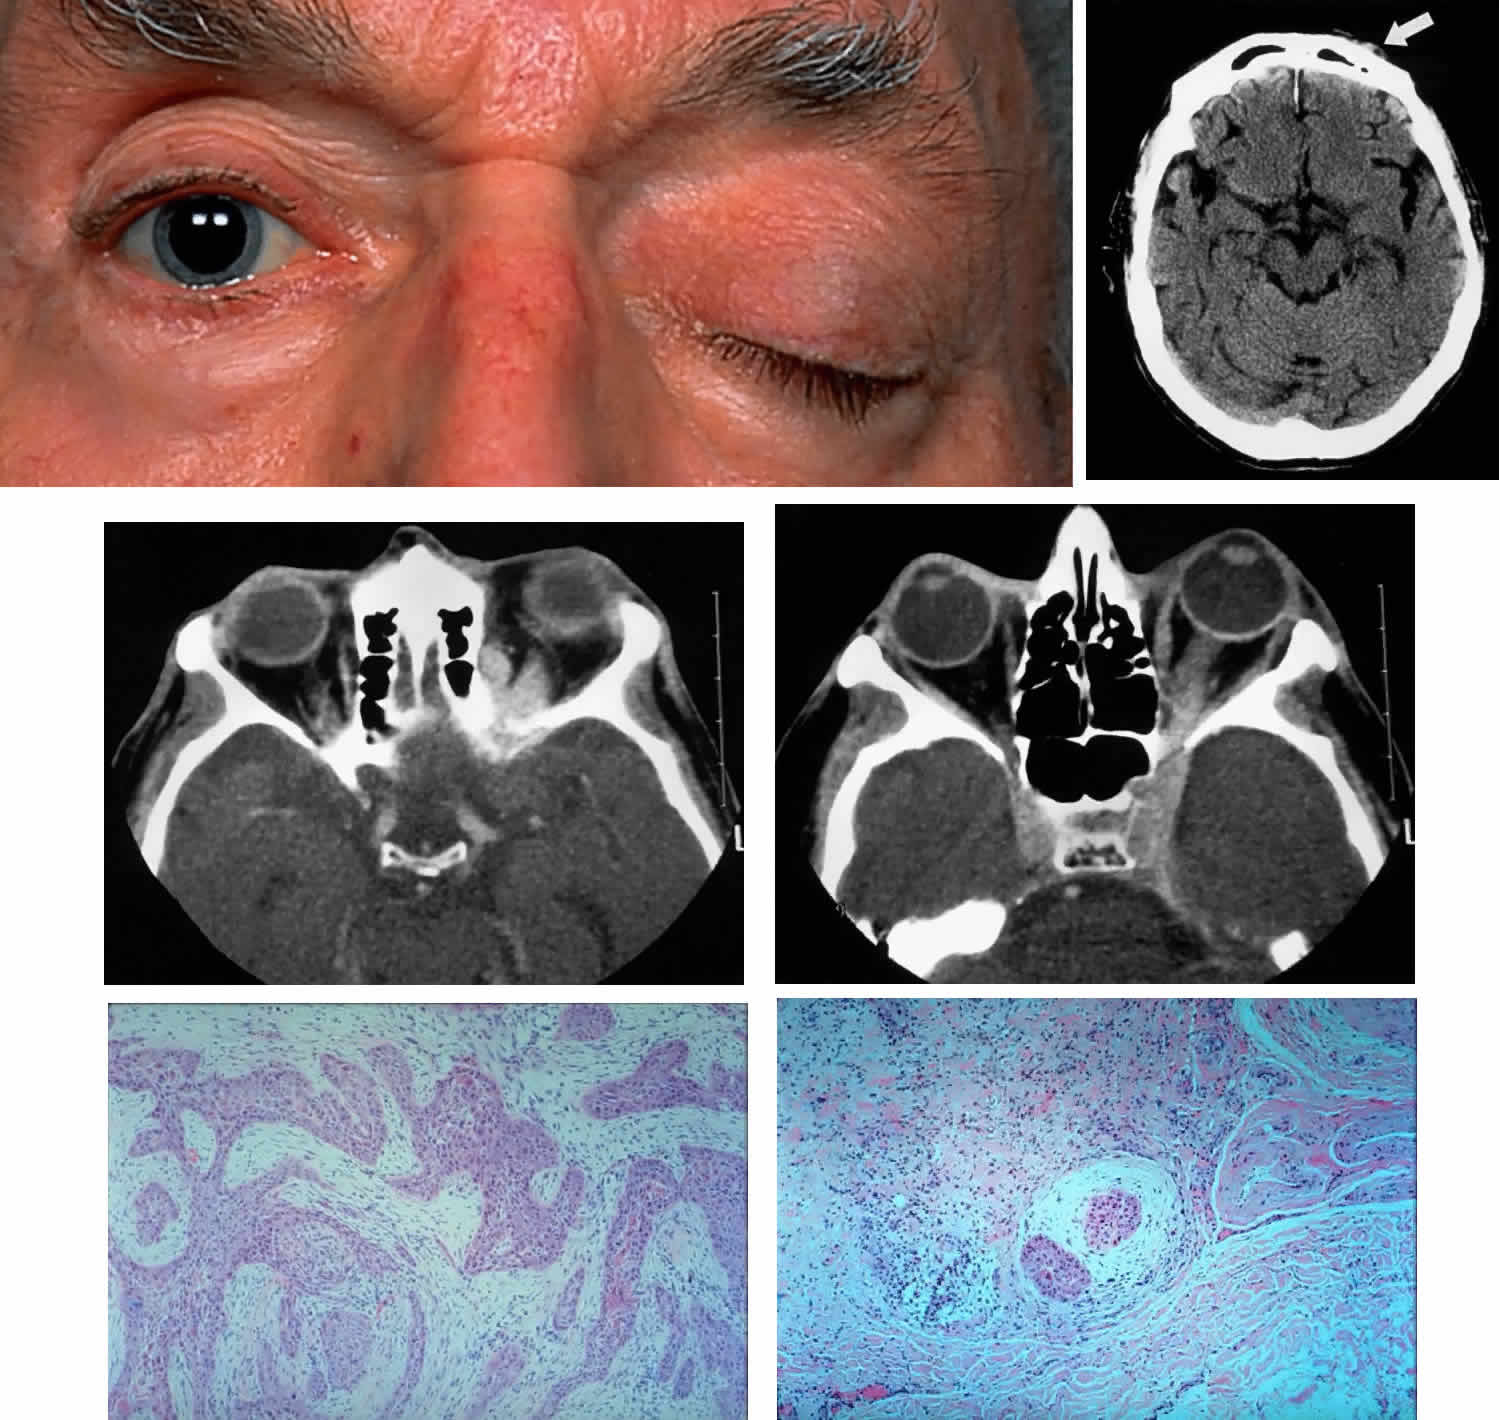

Fig. 8. A 73-year-old man treated 3 years previously with excision of a squamous cell carcinoma in the left supraorbital region had recurrence of tumor, which was again excised. He developed progressive pain and tingling in the forehead, vertical diplopia, and finally general malaise lasting 18 months, ultimately requiring hospitalization. He was treated with corticosteroids for presumed Tolosa-Hunt syndrome, showed minimal improvement, and was discharged. Over a 2-month period, he developed decreased vision, ptosis, and bulging of the eye. On presentation he had vision of 20/80 with a relative afferent pupillary defect. There was hypesthesia in the distribution of cranial nerve V1 and hyperesthesia in V2. He had a palpable fixed cord in the forehead in the distribution of the supraorbital nerve, complete ptosis, ophthalmoplegia, and 7 mm of proptosis (A). CT scan showed local infiltration along the supraorbital nerve (B, arrow), with extension of a soft tissue mass along the orbital roof to the orbital apex (C), through a widened superior orbital fissure, and into the cavernous sinus (D). An orbital biopsy revealed cords of squamous cells (E) (H & E, × 80) and evidence of infiltration inside a small branch nerve sheath (F) (H & E, × 80). A single fraction of 10 Gy was given as palliative treatment for pain control.

Fig. 9. A 79-year-old man had been treated for several years for chronic blepharoconjunctivitis. On examination, he had thickening of upper and lower lid margins, diffuse symblepharon, conjunctival thickening, injection, and yellowish plaque-like foci (A). Conjunctival biopsy confirmed invasive sebaceous cell carcinoma, and subtotal exenteration was performed. Tumor invasion along the globe (B) (H & E, × 32) and into muscle (C) (H & E, × 80) was noted.

Fig. 11. A 61-year-old white man noted a pigment spot in the medial canthal area of his left eye associated with intermittent subconjunctival hemorrhages lasting 6 months. On examination, there was a raised, pigmented lesion in the lower medial conjunctiva (A) measuring 20 mm across the base, with a central, pale, telangiectatic nodule 6 mm thick noted on lateral gaze (B). There was extension into the upper medial fornix and laterally in the lower fornix. There was no evidence of preauricular, submandibular, or cervical lymphadenopathy. A clinical diagnosis of conjunctival melanoma arising in primary acquired melanosis (PAM) was made. Conjunctival biopsy revealed invasive melanoma (C and D) (H & E, × 80 and × 200, respectively) arising within PAM type IB (E) (H & E, × 200). A total exenteration and split-thickness skin graft from the anterior thigh were performed, and the patient was disease-free at 6 months' follow-up.

Fig. 13. A 65-year-old man presented originally with a right retinal detachment and secondary glaucoma due to a large choroidal melanoma. The patient refused enucleation and self-treated instead with herbal medicines and “health foods.” He presented again 6 years later with acute onset of proptosis associated with pain, periocular edema, erythema, and marked restricted ductions (A). CT scan revealed the intraocular tumor, with massive orbital extension and displacement of the globe anteriorly, downward, and laterally (B and C). He underwent lid-splitting exenteration and split-thickness skin graft from the anterior thigh. The gross specimen shows the massive orbital component of melanoma, which had extended from the posterior choroid through emissarial vessels (D). An area of predominantly spindle-shaped melanoma cells with scattered, heavily pigmented macrophages is shown (E) (H & E, × 200). (D and E courtesy of Valerie A. White, MD, Department of Pathology, University of British Columbia, and the Vancouver Hospital and Health Sciences Center.)